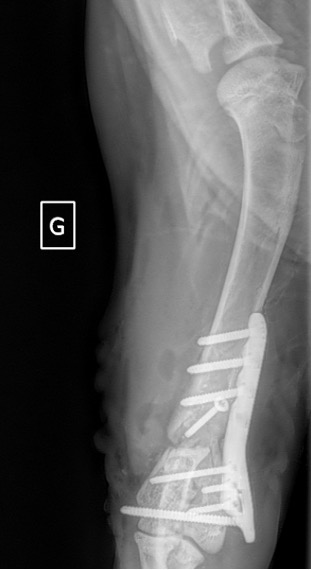

Notre préférence va vers le placement de deux plaques humérales : une médiale de la plus grande taille possible et l’autre latérale, généralement d’une taille inférieure à la première. Dans l’exemple 1 (chat européen), une plaque de 2 mm est utilisée médialement et une plaque de 1,5 mm latéralement. Dans l’exemple 2 (chien Malinois), une plaque de 3,5 mm est utilisée médialement et une plaque de 2,7 mm latéralement.

Exemple 2 :

Figure 7 : Post-Op 2 mois